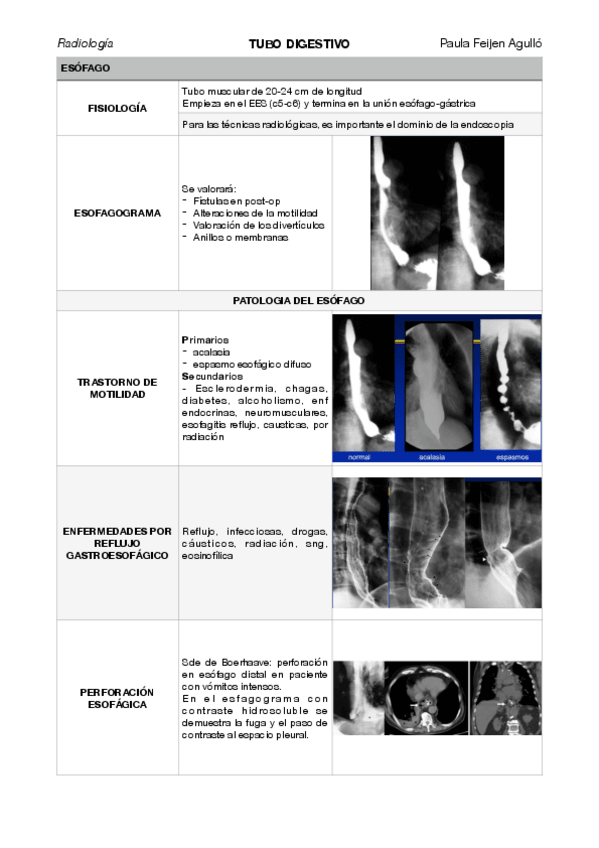

tubo-digestivo.pdf